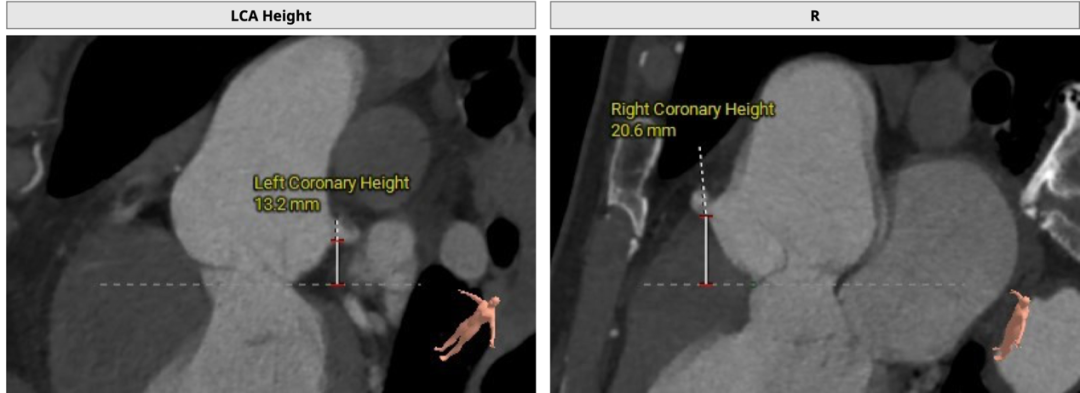

双侧冠脉开口高度可,LCA 13.2mm,RCA 20.6mm:

术中建议造影角度LAO 3°,CAU 13°: